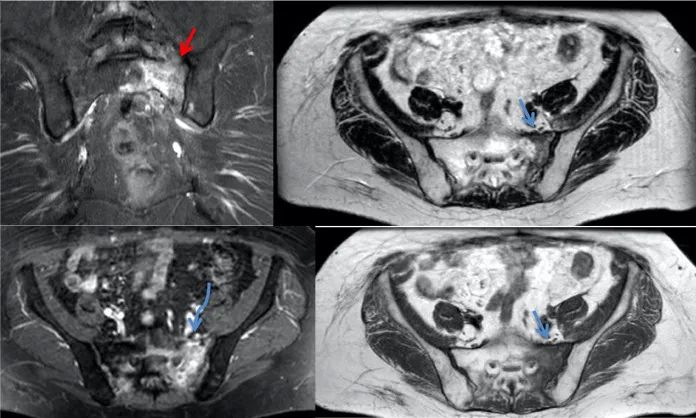

骶骨机能不全骨折 PET/CT 表现

骶骨机能不全骨折的典型 18F-FDG PET/CT 表现为平行于骶髂关节的骨折线伴 FDG 摄取轻中度增高,PET/CT 显示病变的 FDG 摄取特征及形态学改变与转移瘤的鉴别诊断有重要价值。

女,55 岁,宫颈癌放化疗后 5 年发生骶骨机能不全骨折。PET/CT 骶骨横断面(A)、冠状面(B)显示双侧骶骨翼平行于骶髂关节骨折线,放射性摄取弥漫性轻度增高,沿骨折线处为著(箭);矢状面(C)显示骶骨体横行硬化骨折线,轻度 FDG 摄取(箭)